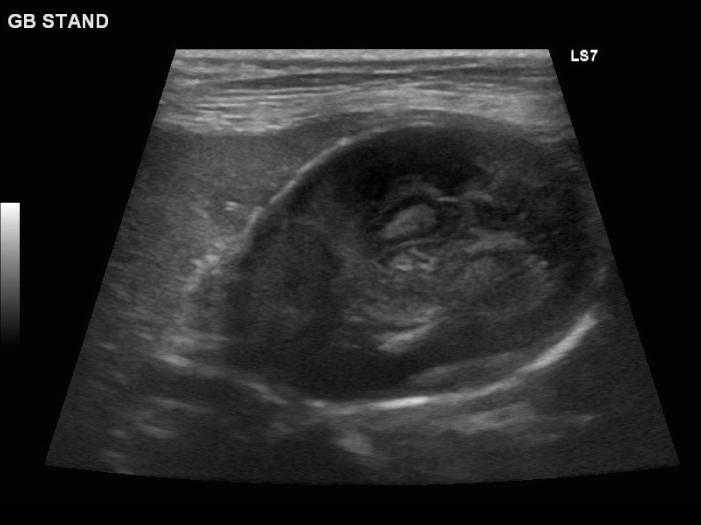

胆嚢粘液嚢腫の場合、エコー検査では放射状に胆泥が胆嚢壁に付着したキウイフルーツ状の所見が見られます。

エコーで胆嚢炎と胆嚢粘液嚢腫であることを確認し、破裂の危険性 を考えて腹腔鏡下胆嚢摘出術を実施することになりました。

臨床症状もなかったので腹腔鏡下胆嚢摘出術